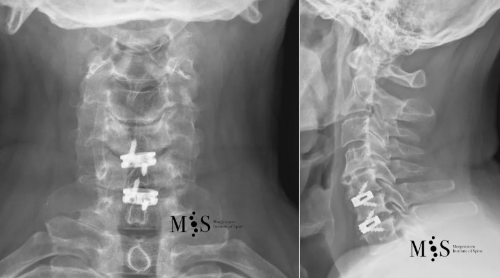

Rx en frente (izquierda) y perfil (derecha) de un implante/caja intersomática

de titanio insertada mediante técnica endoscópica en el nivel C5/C6